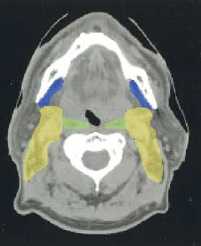

(a–l) Marked lymph nodes (LNs) with each LN group separated by color.

Light blue, submental LN (Ia);

dark blue, submandibular LN (Ib);

yellow, jugular LN (II, III, IV);

red, spinal accessory LN (V);

light green, retropharyngeal LN;

orange, parotid LN;

dark green, anterior jugular LN (VI);

pink, retroauricular/occiptal LN.